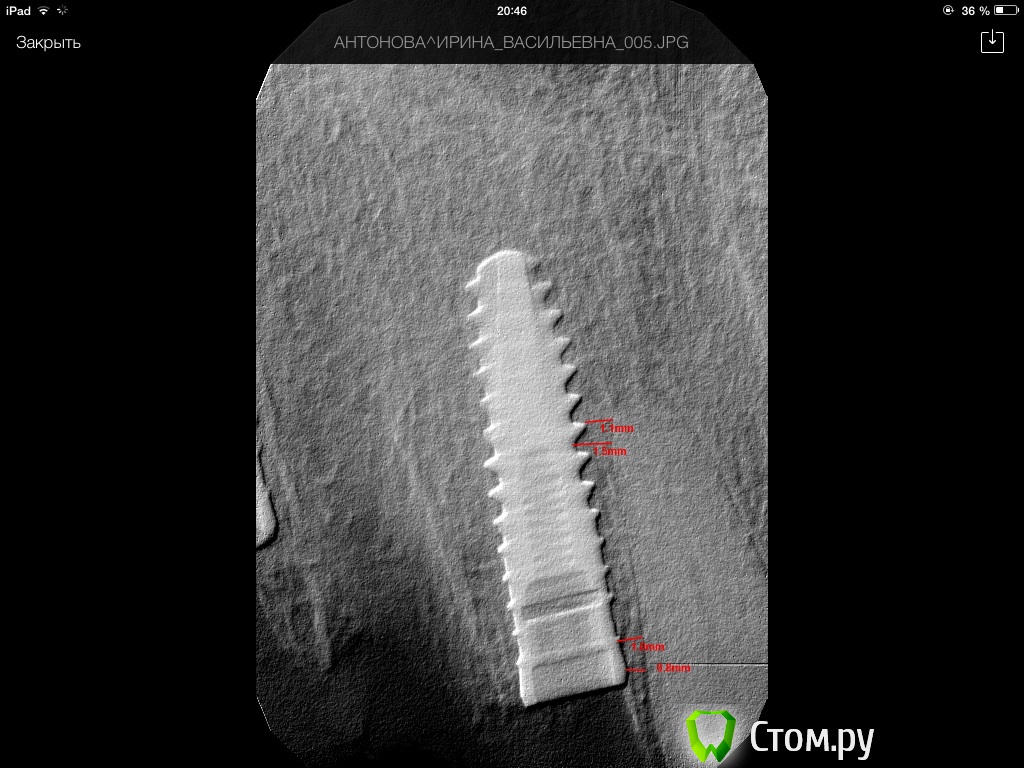

Одномоментная имплантация - премоляр - Semados S-line 3.25*11,5

Всем, доброго времени суток! Чтоб не плодить тему, выложу свой случай! Ставил одномоментно 3,8*13 в области 1.2. Вот что получилось... Есть ли шансы на жизнь у импланта? Кто как думает? Повлияет ли на эстетику??..